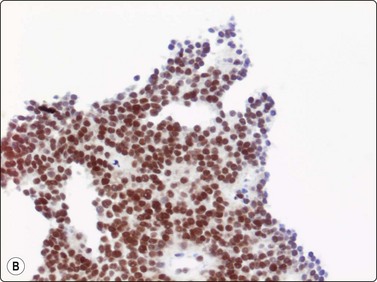

In the precursor lymphomas, nuclei generally are of variable size with irregular or folded contours and the cytoplasm is narrow and pale without vacuoles, but often demonstrates a small clear spot close to the nucleus. The rhabdomyoblast-like cells in alveolar rhabdomyosarcoma are rather distinctive with eccentric nuclei and a dense eosinophilic cytoplasm on wet-fixed smears. The long, thin cytoplasmic processes, often connecting cells, in neuroblastoma are not a feature of conventional ES. However, the differential diagnosis between atypical ES and PNET and poorly differentiated Ewing’s sarcoma-like synovial sarcoma and the above mentioned tumors is much more difficult in routinely stained smears. Cytogenetic analysis is the most valuable diagnostic adjunct.41,42 Immunocytochemistry, including CD99 and FLI-1 are also of value in spite of the fact that both these antibodies are reported to be positive in other malignant small cell tumors (Fig.16.33).

image image

Fig. 16.33 ES/PNET family of tumors

Immunocytochemistry, mainly (A) CD99 and (B) FLI-1 are of diagnostic value (A, B, cell block, immunoperoxidase).